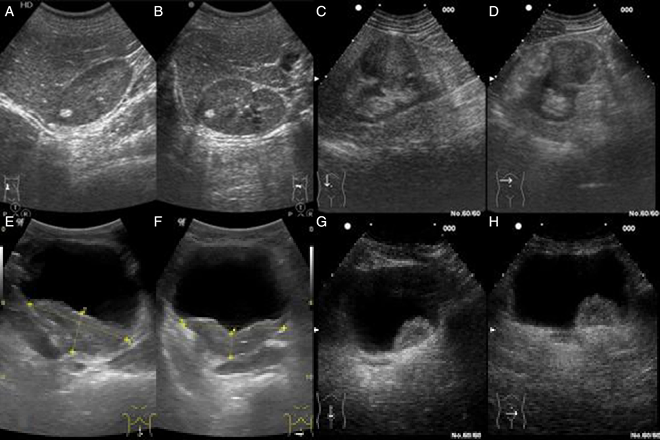

Todos los pacientes evaluados tenían ecografía obstétrica de último trimestre normal. Los criterios para definir infección urinaria es que presentara más de 100 000UI formadoras de colonias en una muestra de orina obtenida por cateterismo vesical. La ecografía posinfeccion se realizo 48hrs después del internamiento, la cistouretrografia se realizo entre las 4 y 6 semanas del diagnostico de infección urinaria. La ecografía renal posinfeccion fue normal en 88.4% de los pacientes, 9.3% mostró leve dilatación de la pelvis renal, en 2.3% fue francamente patológica.

Del total de las cistouretrografias realizadas 32% mostró reflujo vesicoureteral siendo mayores los grado I y II. Los pacientes que presentaba reflujo vesicouretral grado I y II la ecografía fue normal, y los que tenían reflujo grado III y IV la ecografía mostraba dilatación leve. En este estudio la sensibilidad de la ecografía posinfeccion fue del 44%, con una especificidad del 95% para la detección de reflujo vesicoureteral.